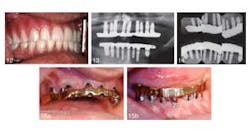

An article in the current issue of the Journal of Oral Implantology looks at long-term treatment for a patient with severe periodontal damage. The authors anticipate that the higher risk of implant failure in this patient will be offset by coating the implants with a rough, oxidized surface called TiUnite and by emphasizing the need for diligent oral hygiene. They also expect that by using overdenture prostheses instead of conventional removable dentures, they will improve stability and function — and thus patient satisfaction. Overall, increased use of implants has improved eating comfort and resulted in few complications after the surgery. However, pressure on implants is suspected to speed up loss of dense cortical bone in the jaw. Research has shown the TiUnite material stimulates bone growth, leading to faster fusion of implants and surrounding jawbone.RELATED | New material used in molar extraction sites optimizes bone regeneration and dental implant stability The current article is a case report on a 51-year-old patient who had been in a motorcycle accident and has a history of herpes, hepatitis, insulin-dependent diabetes, and persistent recurrent tooth decay. The patient’s remaining teeth (see photos below) were comprised of fractured crowns and older failing implants. The surgeons removed all of his teeth and old implants followed by the immediate insertions of new implants and stabilizing overdentures. Provisional implants were used for support during healing. Five months later, the interim provisional implants and prosthesis were removed and fabrication of a final restorative prosthesis was initiated.

RELATED | Atrophic patients have more options with new dental implant Despite the higher risk of implant failure due to his periodontal disease and diabetes, the patient’s implants have been in place for 12 years with no complications noted at routine checkups and cleanings. The patient has been instructed post surgery in proper use of floss threaders, deep-cleaning brushes, and an oral irrigator. His daily efforts to practice good oral hygiene improved his overall dental health. The patient was pleased with the results one week after the provisional implants were placed and was still happy with the surgery 12 years later. Little care and maintenance of the prostheses have been necessary.RELATED |Less invasive approach to dental implants allows heart patients to continue anticoagulation therapy